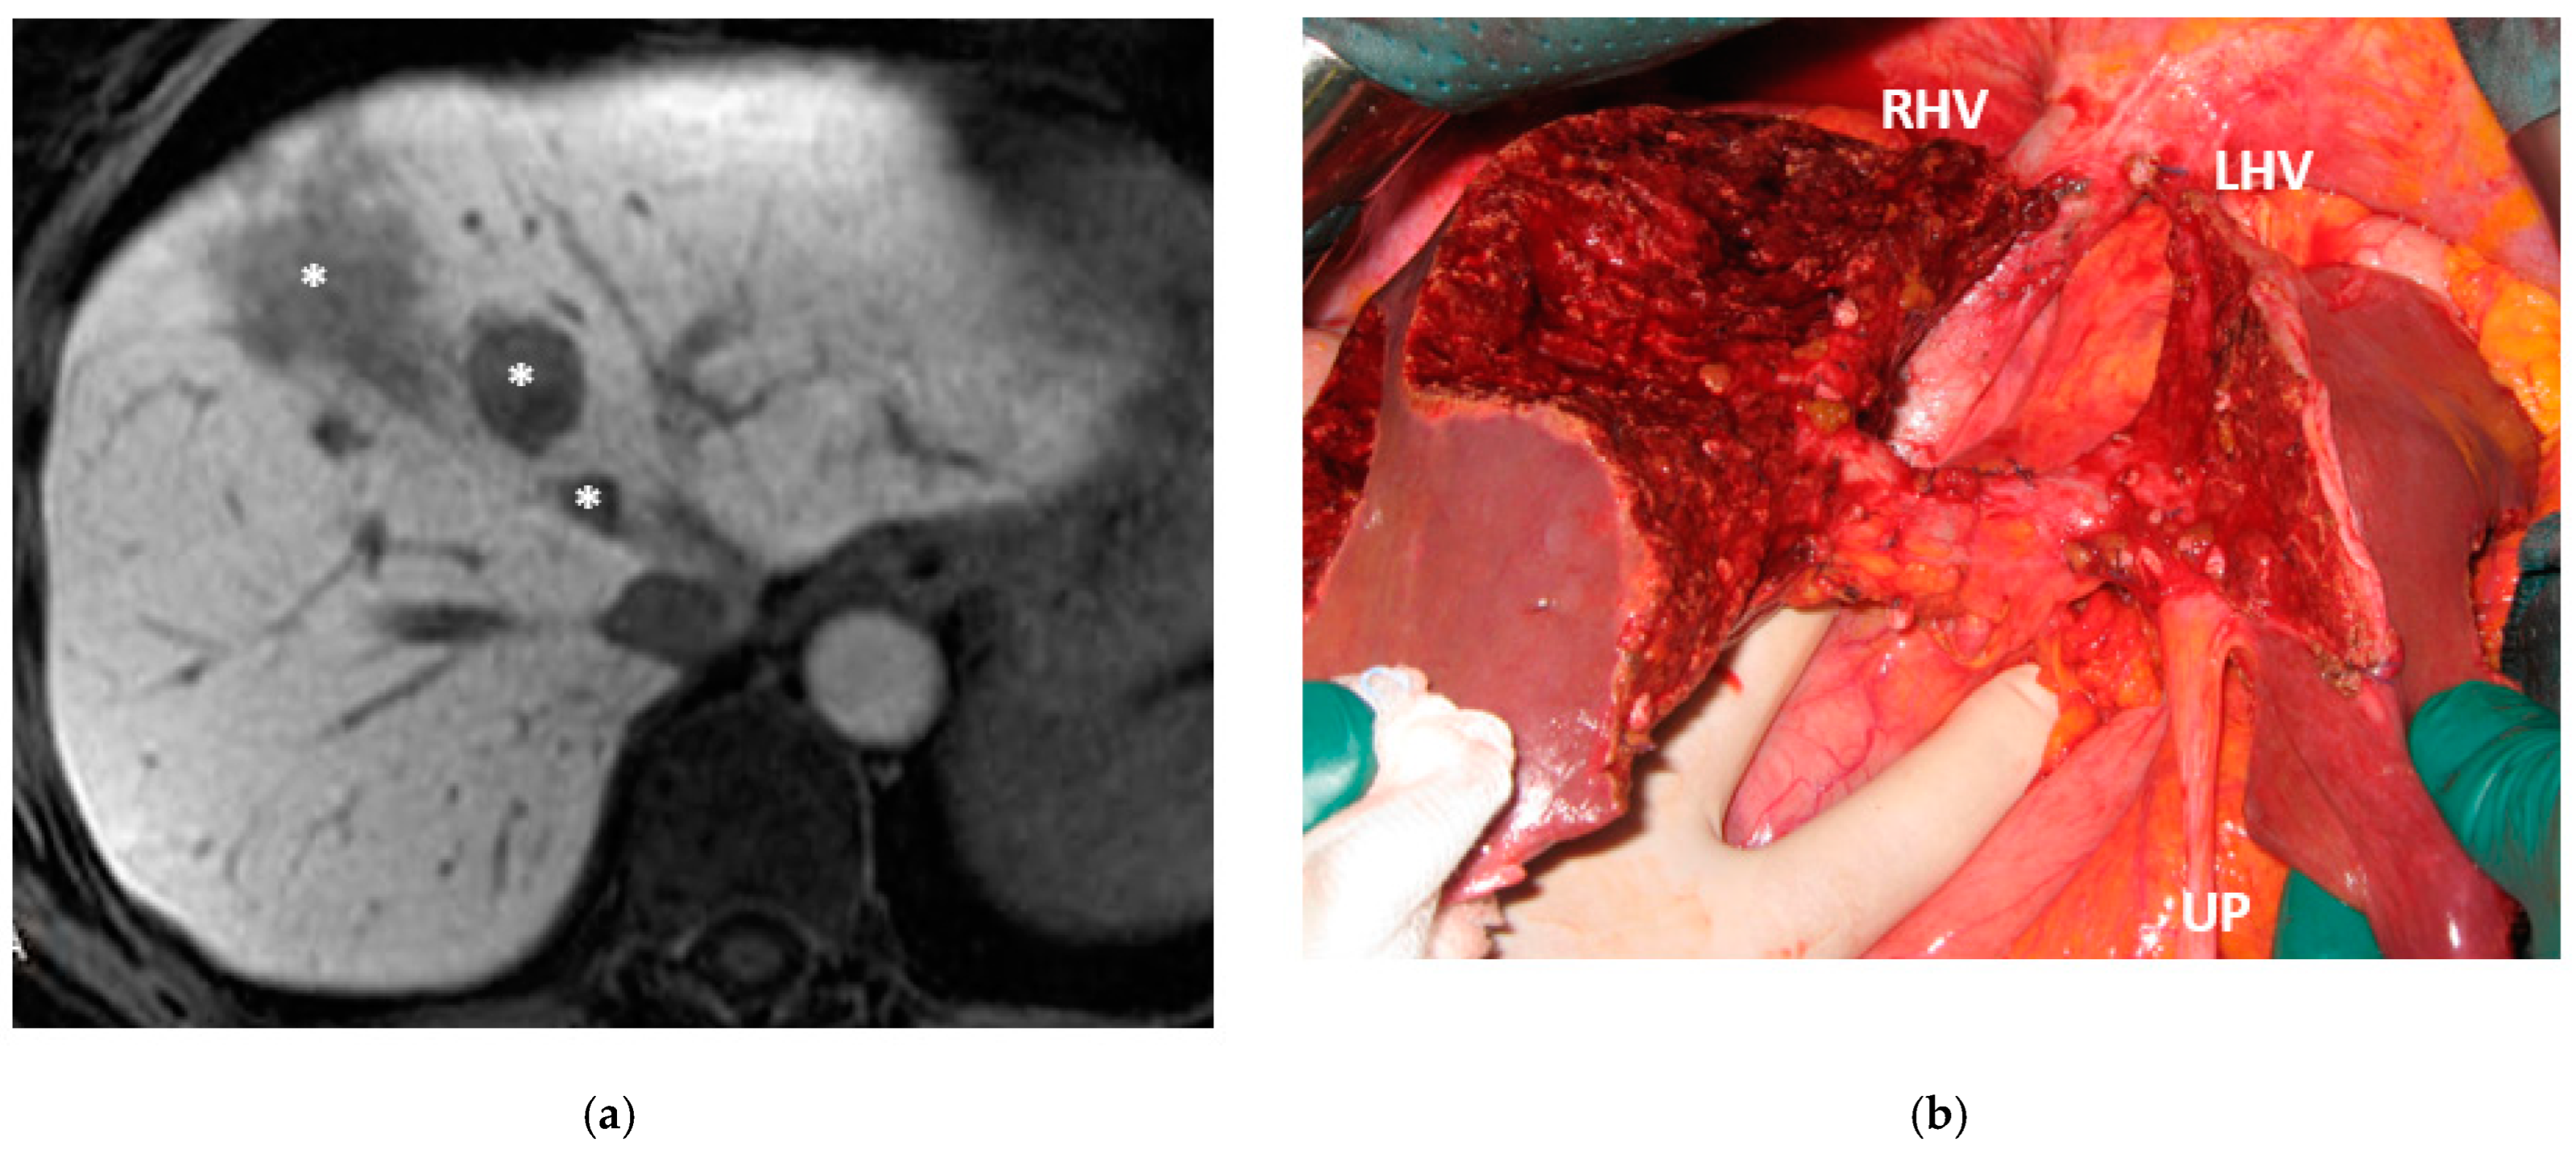

In six patients the resection of first-order GP was planned and e-ALPPS was performed. Four e-ALPPS were parenchyma sparing since a part of S4 was preserved (in deportalized liver in one case of FLR = part of S6/S7, see Figure 9).

In four cases the Spiegel lobe was preserved. At the first stage (MLP) MHV was resected in four cases, preserved in deportalized liver in the case of FLR = part of S6/S7 and reconstructed with an end-to-lateral anastomosis with LHV (FLR = S4b/S2/Spiegel lobe) in one case. In two patients (FLR 15% = part of S4/S2 and Spiegel lobe; FLR 7% = part of S2/S3) FLR volume was deemed inadequate after the first step of e-ALPPS (FLR 29% and 28%, 15 and 17 days after the first stage), daily liver growth after the first stage was 21 mL/day in the first 8 days and 8 mL/day in the subsequent 7 days in one case and 19 mL/day in the first 17 days in the other (in the latter, growth kinetic cannot be evaluated during the first week since CT was not performed). Intermediate stage of partial resection of the deportalized liver was performed (in both cases resection of S5-S8, in one case en-bloc with RHV which was reconstructed with an end-to-end anastomosis). Seven days after the intermediate stage FLR volume increased up to 39% and 41% with a daily growth of 18 mL/day and 25 mL/day. The third stage to complete the ALPPS procedure was performed (23 and 27 days after the first stage) resecting the last part of deportalized liver (S6/S7). In both cases the left hemicolectomy was associated to third step of staged e-ALPPS (see Figure 10, Figure 11, Figure 12 and Figure 13).

In a case of e-ALPPS an intermediate stage of PSH of the deportalized liver was necessary (due to inadequate FLR volume of S2/S3 18 days after the first stage), at the intermediate stage S5/S8 were resected en-bloc with RHV which was reconstructed with an end-to-end anastomosis (Figure 11).

In a case of e-ALPPS at the first stage, S4b was preserved and MHV was reconstructed with an end-to-lateral anastomosis with LHV.

Taking into account that the liver can be considered a paired organ, we introduced the concept of e-ALPPS when first-order GP resection is planned and FLR volume is deemed insufficient. ALPPS is defined as enhanced because liver partition is obtained with two full thickness transection lines (MLP) instead of the single line as described in the classical ALPPS [6] with the advantage of leaving a well-vascularized liver parenchyma with no possibility for parenchymal debris. We have added to ALPPS the parenchyma-sparing concept, expanding the novelty introduced by Botea et al. [20] of preserving S4 whenever possible including the deportalized liver (Figure 9).

To date, in our institution, liver function evaluation with 99mTc-mebrofenin hepatobiliary scintigraphy is not available and liver volume is still the way to determine the adequate FLR [32]. In two cases of e-ALPPS (Figure 10, Figure 11, Figure 12 and Figure 13), adequate FLR was not achieved after the first stage despite MHV resection, which is considered a procedure accentuating FLR volume hypertrophy [33]. Our MDT, observing FLR volume increase after the resection of embolized liver in PS-TSH with SS-PVE, proposed the partial resection of deportalized liver as a boost for FLR regeneration up to the adequate volume. We observed for the first time a FLR volume increase beyond the classical ALPPS technique [6], which is considered the most powerful liver augmentation technique [34]. The regeneration observed is completely independent of the venous system and it is not possible to advocate the same mechanism of PVE, PVL or liver deprivation. The arterial system is most probably responsible for the observed volume increase and this is supported by Zhuo et al., who observed the same in a case of hepatic arterial infusion chemotherapy and arterial embolization in the deportalized liver with a huge HCC and inadequate FLR hypertrophy one month after stage 1 ALPPS [35].